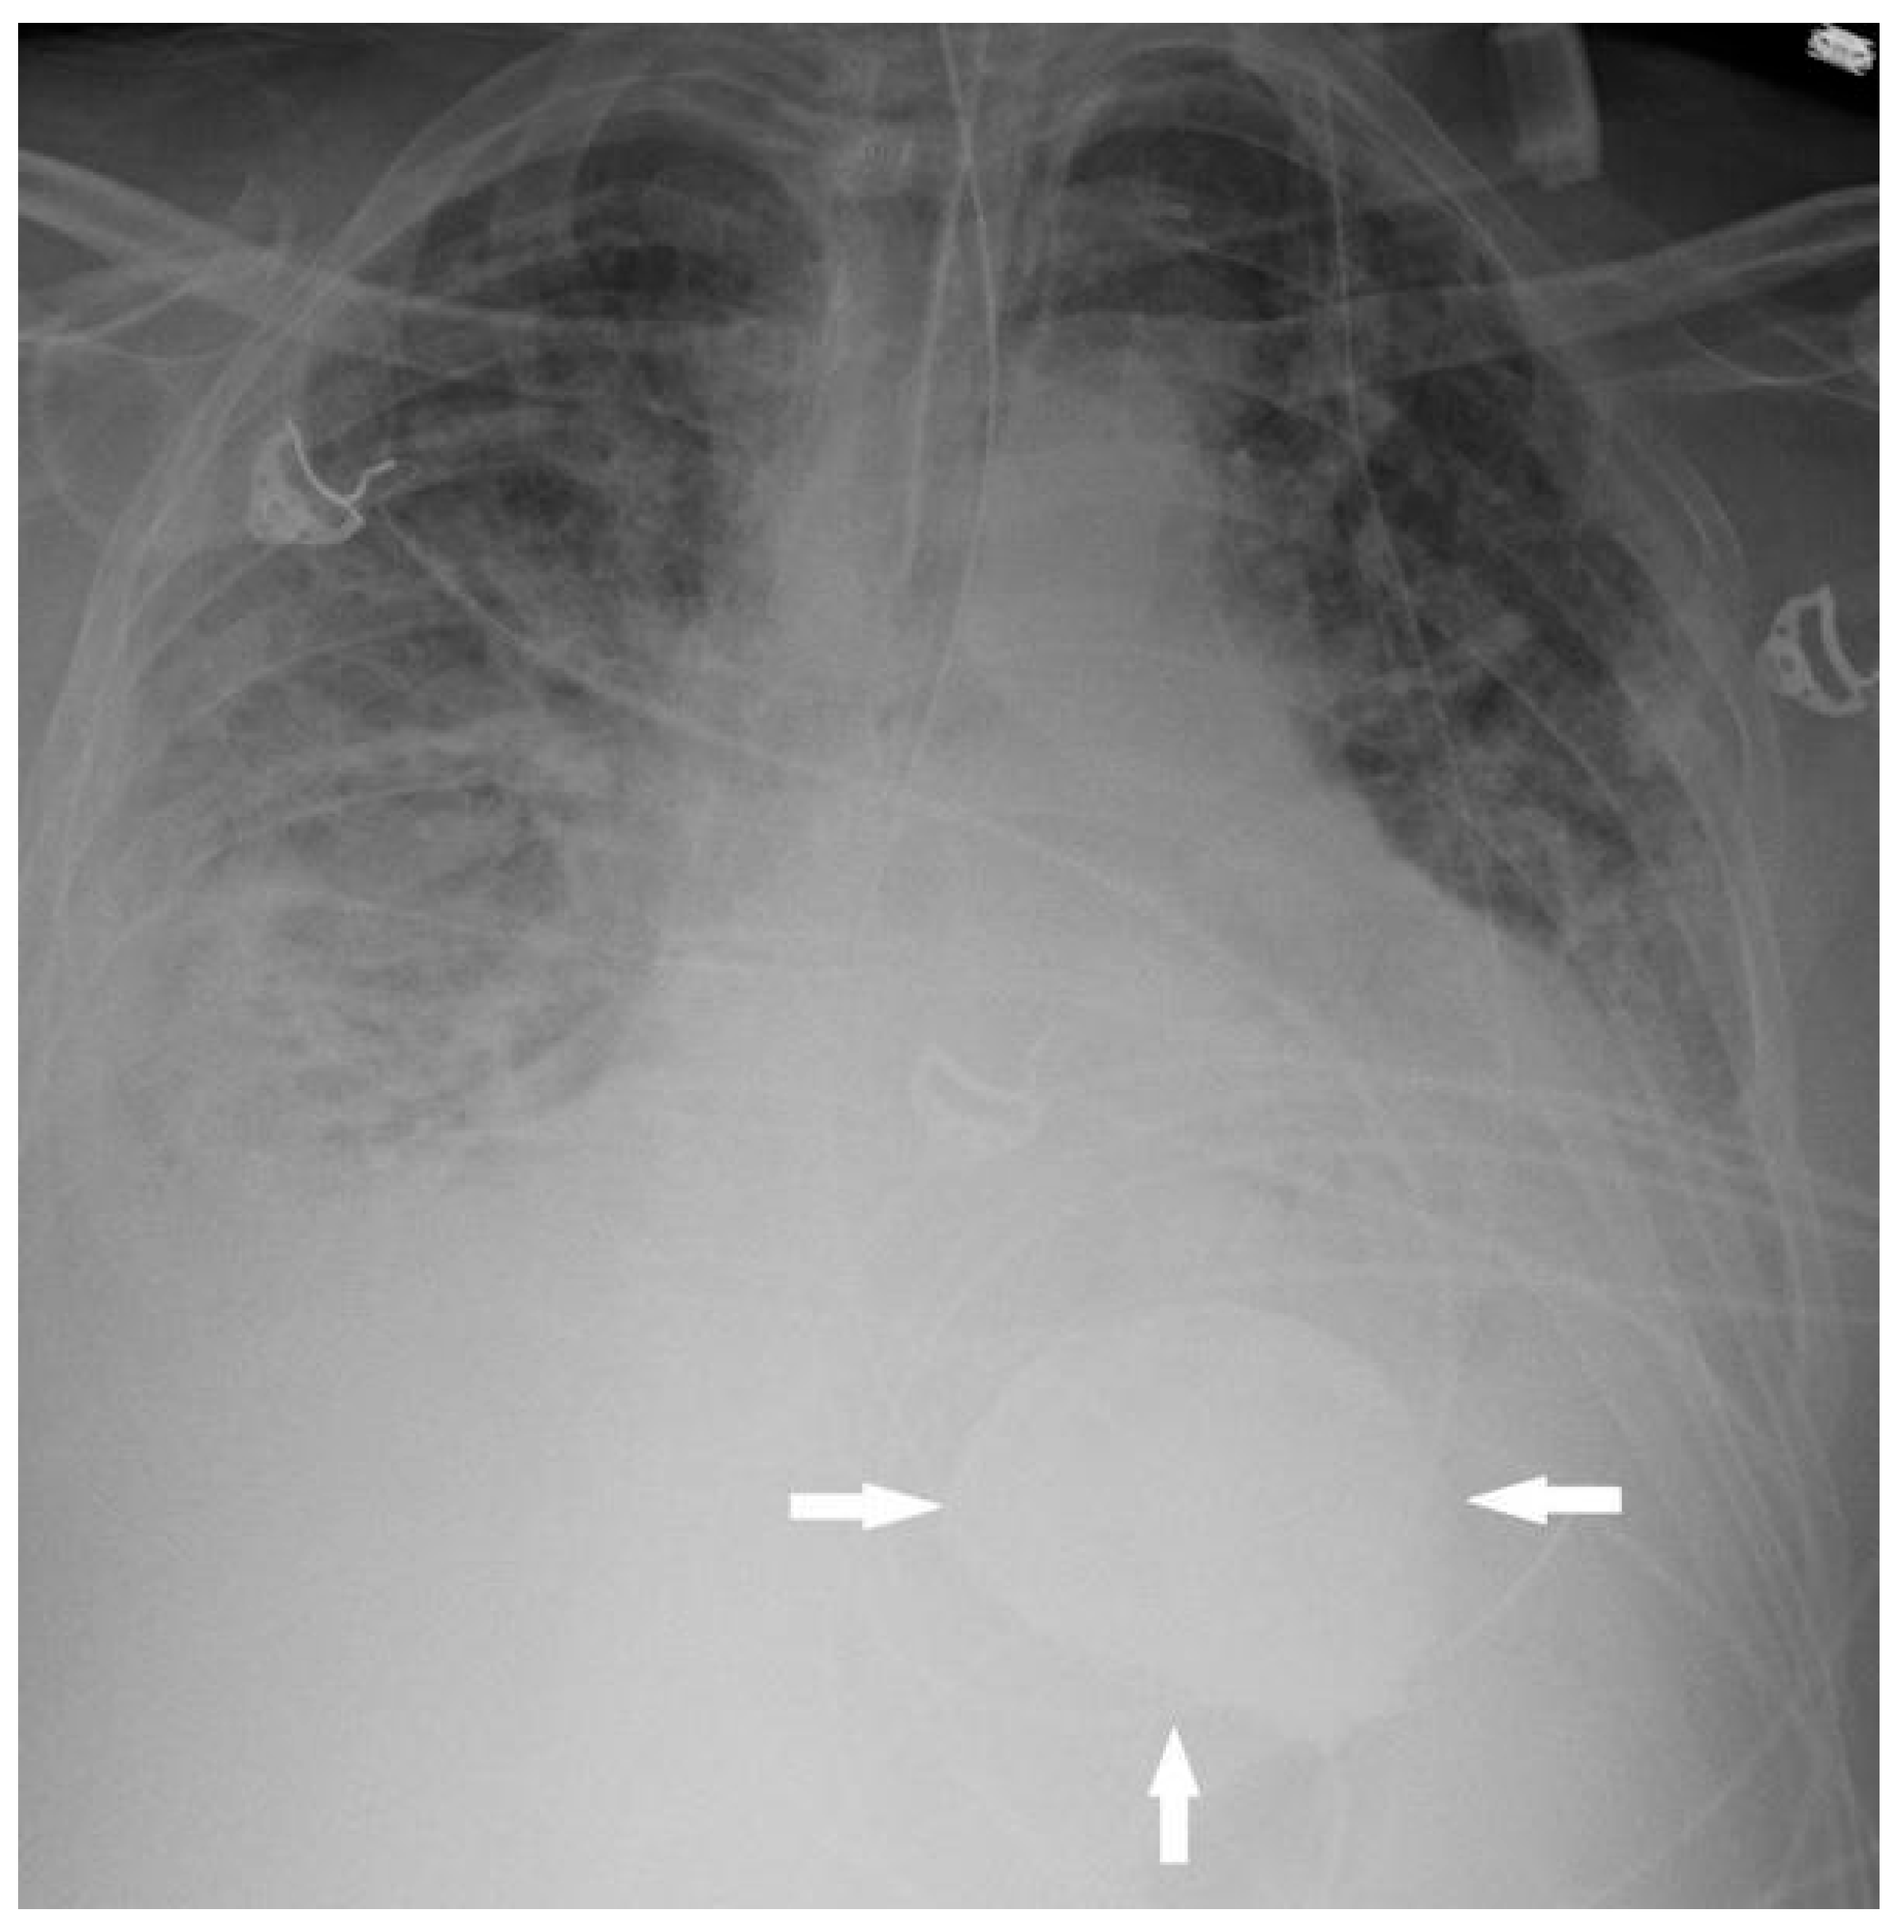

Sodium Zirconium Cyclosilicate in the Gastrointestinal Tract Mimicking an Acute Gastrointestinal Bleed on CT